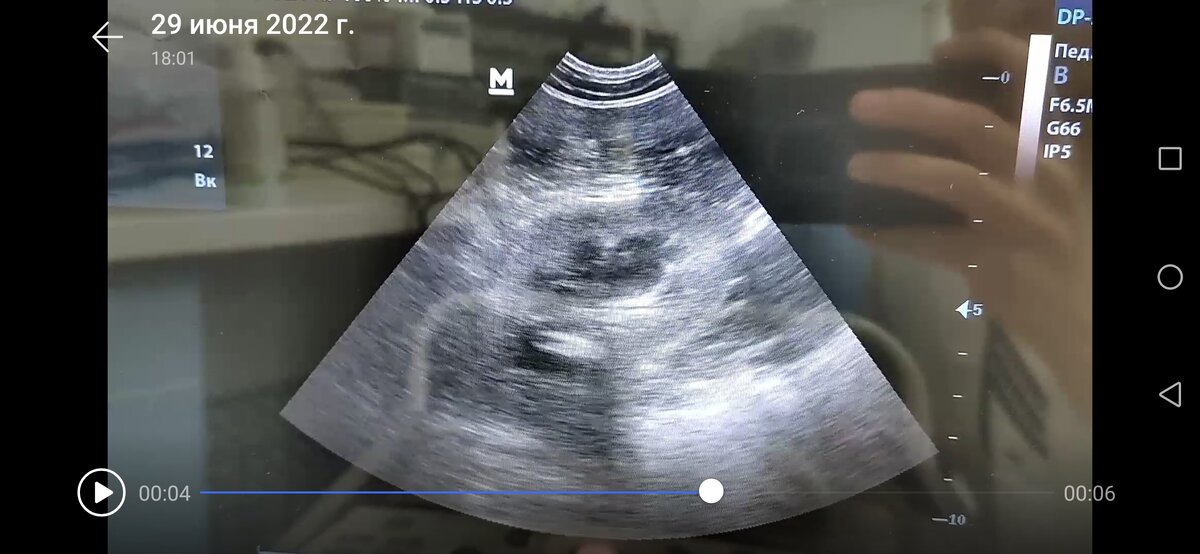

1. Признаки цистита с неоднородным крупнодисперсным содержимым смешанной эхогенности, что соответствует кровяным сгусткам, или клеточному содержимому, кроме того утолщена стенка мочевого пузыря. Для дальнейшей диагностики необходимо сдать мочу на анализ и определить качество осадка.

2. УЗИ признаки хронического процесса в обеих почках, за счет усиления эхогенности коркового слоя, который изоэхогенен селезенке. Для дальнейшей диагностики необходимо сопоставить данные с биохимическим анализом крови.